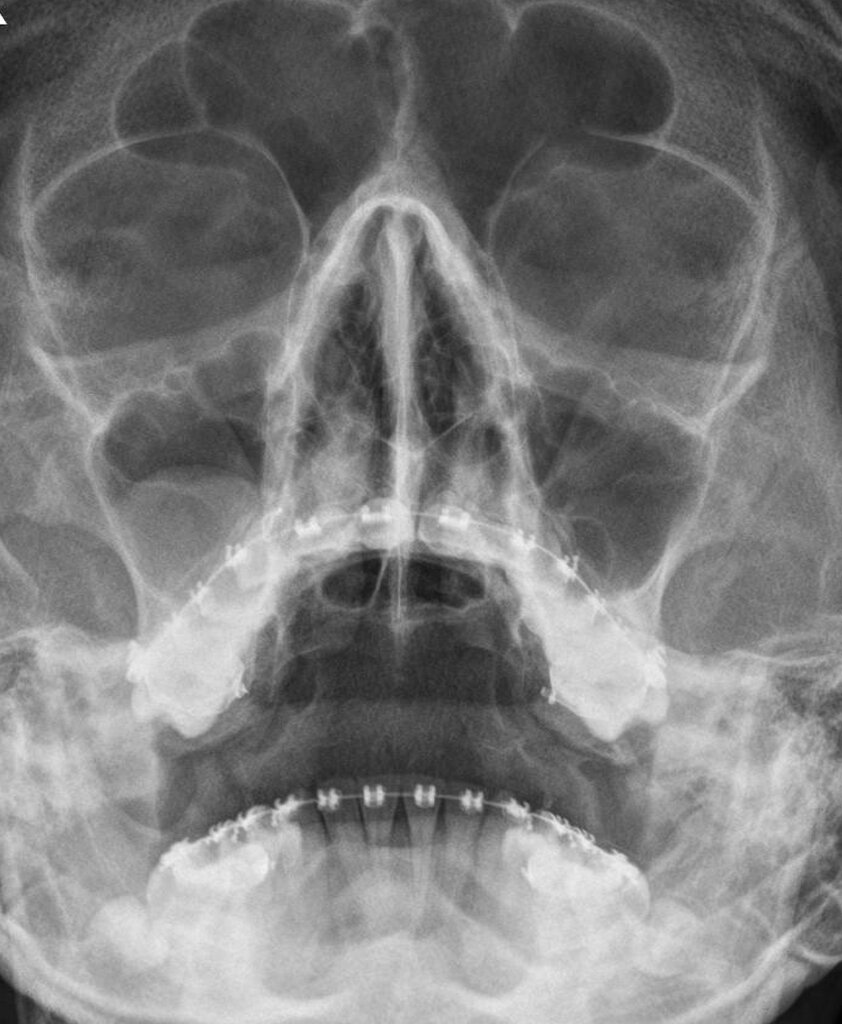

Такие случаи крайне редки. За период 50 лет в медицинской практике известно лишь 26 подобных ситуаций. Одной из последних была с 59 летним пациентом из Дании. Мужчина на протяжении 2-х лет страдал заложенностью носа и периодически наблюдал белые выделения из носовой полости. Как оказалась в носу был вросший зуб. Как он там оказался история умалчивает.